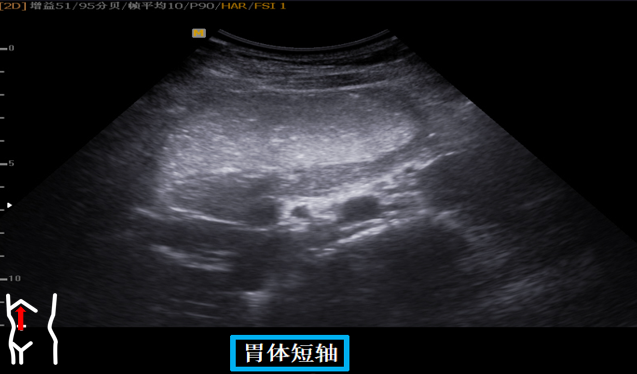

第三组胃体切面

患者取右侧卧位探头从左肋缘下朝左上方翘找出脾下缘以其为起点原位逆时针扇扫依次可见胃底贲门胃体长轴短轴胃体胰腺胃角长轴胃角短轴胃角切迹是胃体与胃窦分界这组切面同时可以观察到胃窦有时还可以观察到球部。